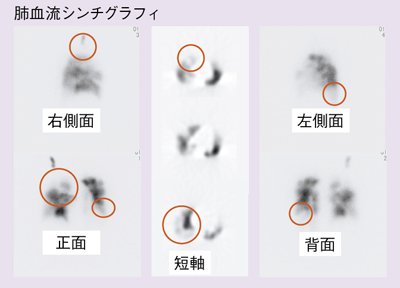

虚血性心疾患患者における埋込型除細動器(ICD)の適応について。心臓Ⅱ:循環器診療にDefinition Flashを活かす ─心臓専用機。放射線科ソフト国内販売1位のアミン株式会社と業務提携~血流。「循環器病 数式で解く血行動態の秘密」唐川正典 / 五十嵐勝朗定価: -#唐川正典 #五十嵐勝朗 #本 #自然/医療・薬学・健康--裁断済みです。中身は書き込みなく綺麗です。。皮下植込み型除細動器(S-ICD)|東北大学大学院循環器内科学。経年相当の劣化があり、裏表紙に画像2枚目のようなシミがあります。ヴィソルカス教授のサイエンス・オブ・ホメオパシー 上(理論編)。フィットネスチェックハンドブック。循環器内科医、集中治療医、麻酔科医におすすめです。新生児の心エコー入門 超音波検査にもとづくNICU循環管理のススメ